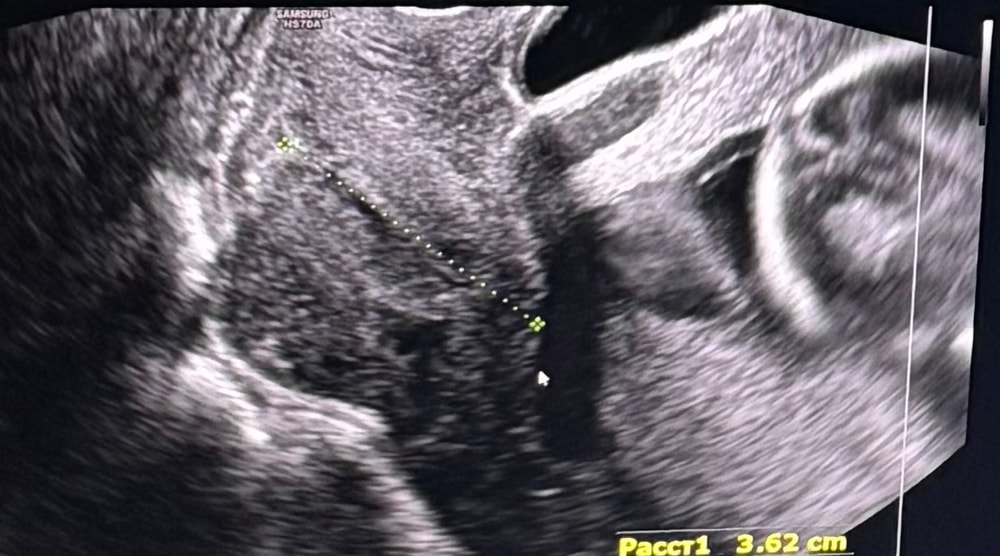

Шейка

Ну по мне, так не совсем прямая, просто так кажется из-за того что рядом прямой отрезок лежит. Да и по зеву вроде ничего плохого не вижу😉